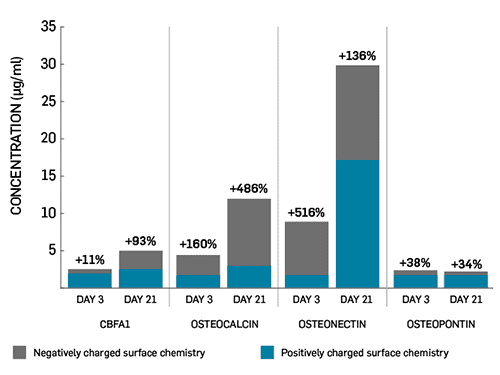

Enhances the osteogenic response to accererate bone growth – 5x normal levels6

References:1.Yang, H.L., et al., Bone healing response to a synthetic calcium sulfate/beta-tricalcium phosphate graft material in a sheep vertebral body defect model. J Biomed Mater Res B Appl Biomater, 2012. 100B(7): p. 1911-21.2.Data on file, Mr A Nissar and Mr S Gopal.3.Data on file, Mr HK Sharma.4.Pina, S. and J.M.F. Ferreira, Bioresorbable Plates and Screws for Clinical Applications: A Review. Journal of Healthcare Engineering, 2012. 3(2).5.Cooper, J.J., J.A. Hunt, and F. Pu, Enhancing the Osteogenic Potential of Bioabsorbable Implants through Control of Surface Charge., in Society for Biomaterials 2007 Annual Meeting. 2007: Chicago, Illinois, USA.